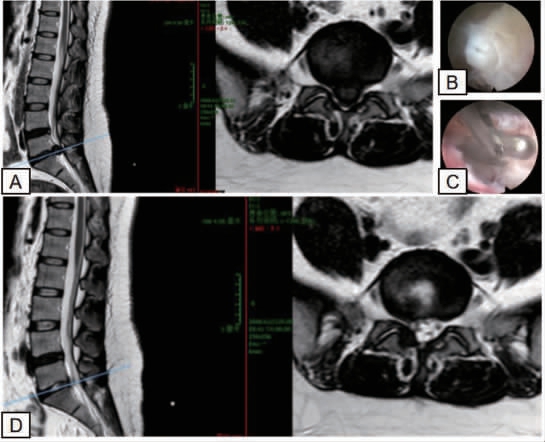

术前患者腰椎磁共振成像(magnetic resonance imaging,MRI)提示L5/S1 巨大突出,硬膜囊明显受压,相应椎管狭窄(图1A)。手术过程:以L5/S1 经椎板间隙入路为例,患者硬膜外麻醉成功后,患者俯卧于手术台,腹部悬空,屈髋屈膝位消毒、铺巾。于L5/S1 右旁2 cm处经皮用注射器针头在C 臂机确认引导下定位椎间隙。随后于L5/S1 椎间隙穿刺针处作皮切口,约0.7 cm,铅笔头套管扩张,放置好椎间孔镜工作通道,经工作通道和椎间孔镜下取出突出变性椎间盘髓核组织(图1B~C),动力磨钻下行L5/S1 椎管减压,扩大成形术,射频消融于纤维环消融成形,神经根粘连松解,彻底减压后,检查漂浮试验(+),经椎间孔镜L5/S1 作通道注射甲泼尼龙琥珀酸钠40 mg 防止术后神经根水肿,促进神经功能恢复。经平车送回病房。术后半年复查腰椎MRI 提示髓核摘除良好(图1D)。本研究经深圳市中医院医学伦理委员会批准。

图1 患者不同时期腰椎MRI

A:术前腰椎MRI 提示L5/S1 巨大突出,硬膜囊明显受压,相应椎管狭窄;B、C:术中镜下可见突出的髓核组织及术中操作;D:术后半年复查腰椎MRI 提示髓核摘除良好。MRI:磁共振成像。